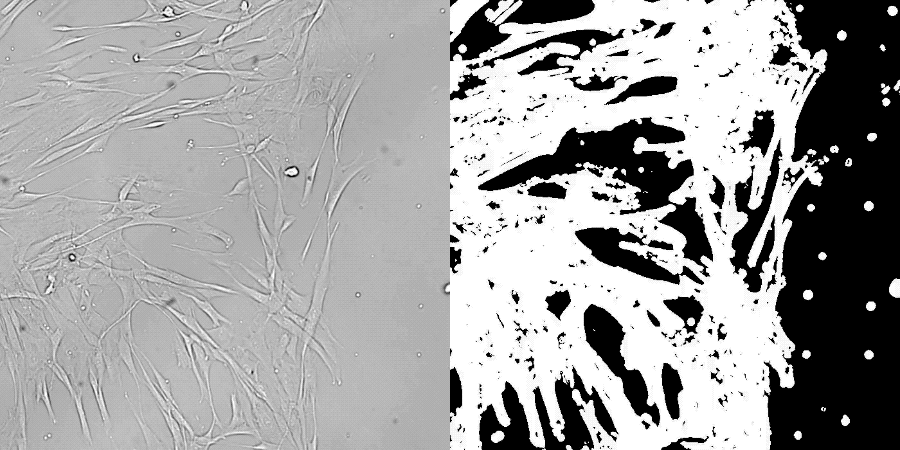

此次研究对象是人类皮肤中的成纤维细胞,这种细胞负责分泌胶原蛋白,在伤口愈合中也有重要作用。

在中间阶段,成纤维细胞的形态和基因表达水平发生变化,去除后再次回到成纤维细胞状态。

一通操作下来,使用表观遗传时钟和基因转录物读数两种方法测量,重编程后的细胞大致与年轻了30岁的细胞特征匹配。

在体外伤口愈合实验中,也观察到重编程细胞恢复了活力,能分泌更多胶原蛋白,迁移到伤口的速度也加快。